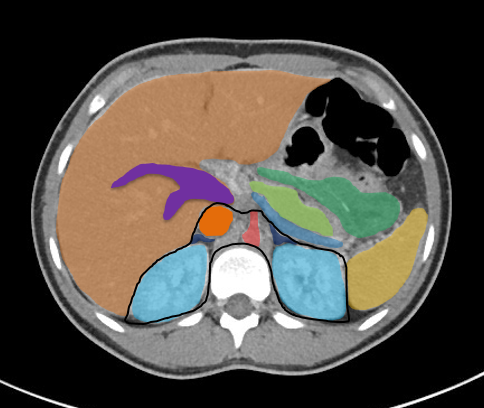

In der interventionellen Radiologie beschränkt sich die Tätigkeit des Radiologen nicht allein auf die bildgebende Diagnostik. Vielmehr übernimmt er eigenständig minimalinvasive Eingriffe und trägt dabei die Verantwortung für die prä-, peri- und postoperative Versorgung der Patient: innen.